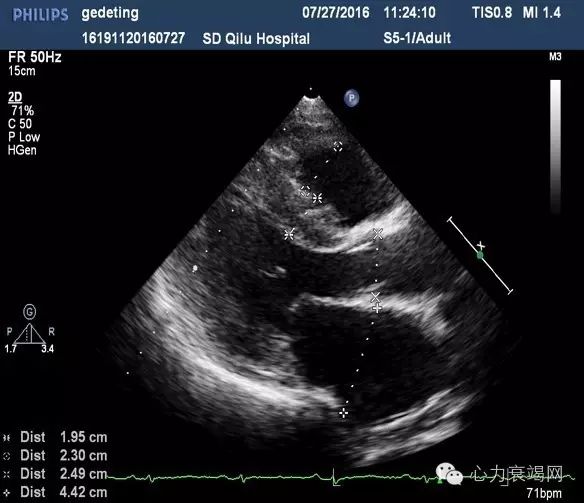

【辅助检查】—心脏超声

IVS 15mm,LVPW 14mm

LVEF 37%

肺动脉高压(中度)

E/e’=21舒张功能减低

提示:心肌病变(病因请结合临床)

IVS 15mm,LVPW 14mm,左室侧壁15mm 心尖部13mm;左室心肌回声不均匀;LVEF 35% ,双房扩大,肺动脉高压(中度)E/e’=21 舒张功能减低

提示:心肌病变淀粉样变心肌病待排?

▶左右心室腔偏小,左心室后壁及心室间隔增厚,心肌回声呈毛玻璃样,室壁运动僵直,双心房扩大

▶心房壁、房间隔及心脏瓣膜也不同程度的增厚

▶舒张功能指标减低